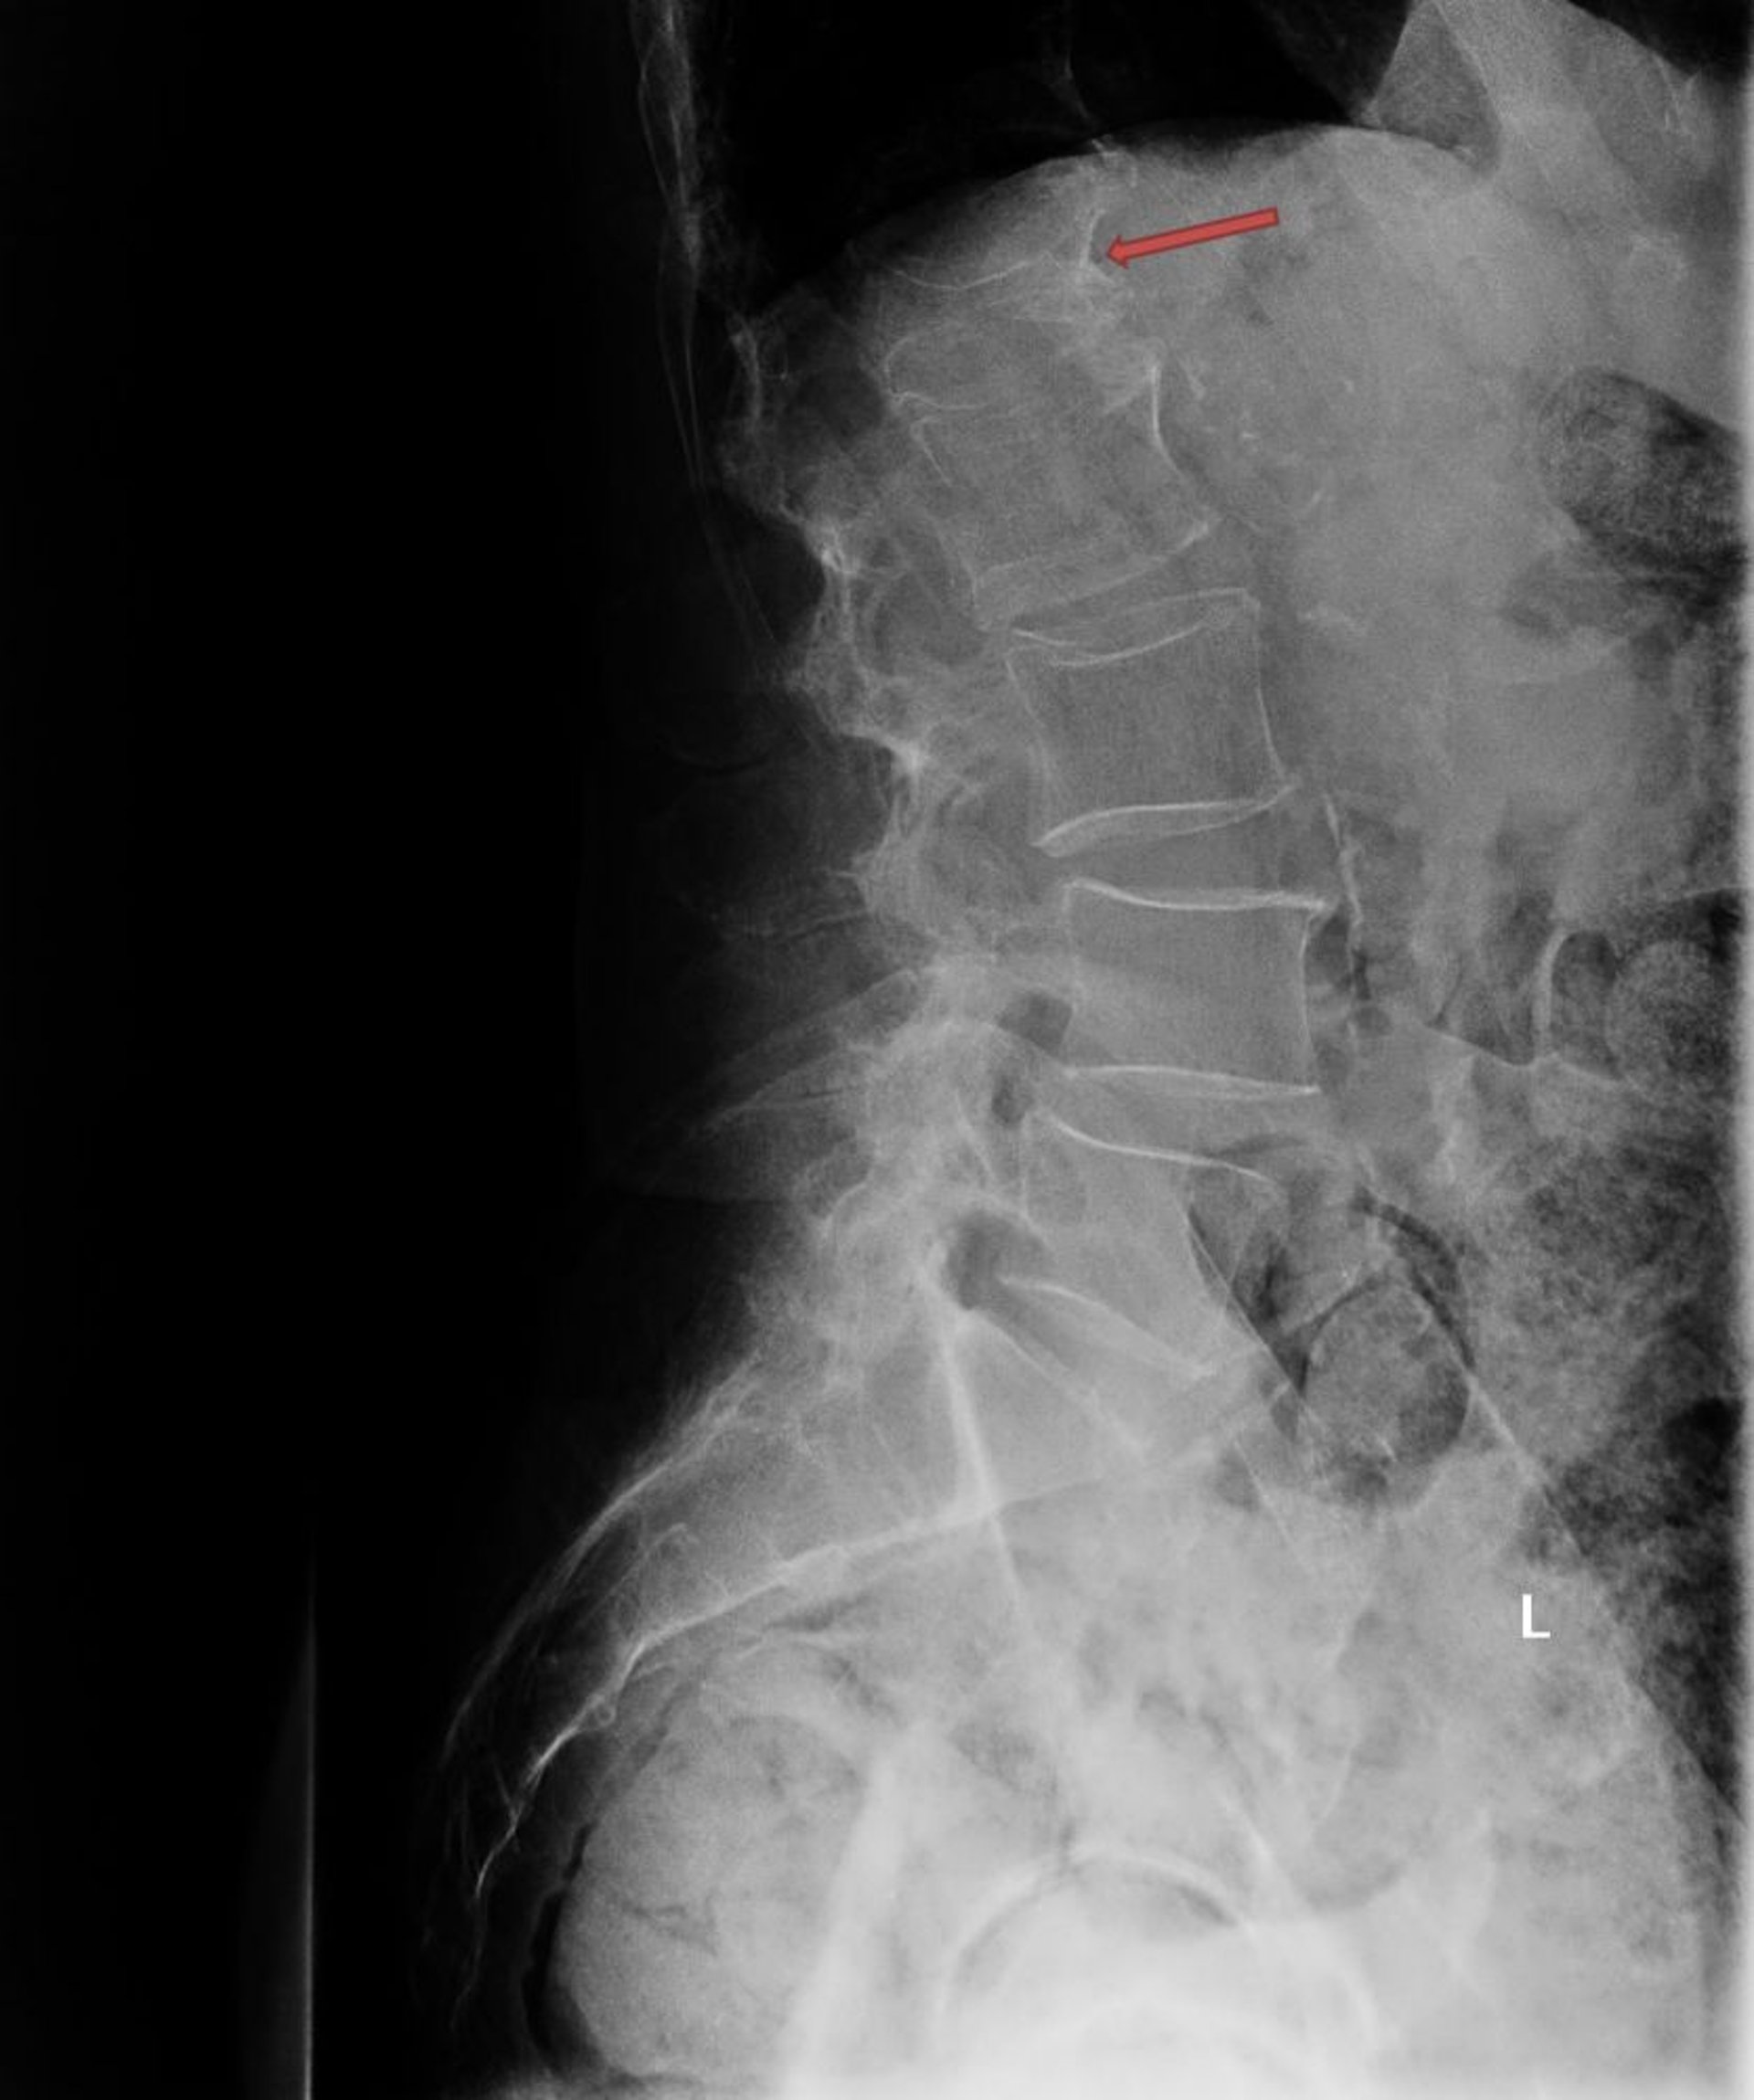

Рентгенограммы

При остеопорозе кости обычно характеризуются сниженной рентгеновской плотностью и утратой трабекулярной структуры, однако эти признаки недостаточны для постановки диагноза. Тем не менее рентгенограммы важны с целью документирования переломов в результате потери костной массы. Уменьшение высоты тела позвонка и увеличение двояковогнутости вертикальных поверхностей его тела характерно для компрессионных переломов позвонков. Переломы грудных позвонков могут привести к заклиниванию передней части кости Переломы позвонков чаще всего возникают на среднегрудном уровне из-за остеопороза (6). Переломы позвонков выше средней части грудного отдела позвоночника должны наводить на мысль о злокачественном новообразовании или травме в качестве этиологической причины. С целью выявления бессимптомных патологических переломов позвоночника у пожилых пациентов с тяжелой болью в спине и локализованной болезненностью в районе остистых отростков позвоночника, а также у пациентов, которые сообщают об уменьшении роста на более чем 3 см, должна быть рассмотрена рентгенография позвоночника.